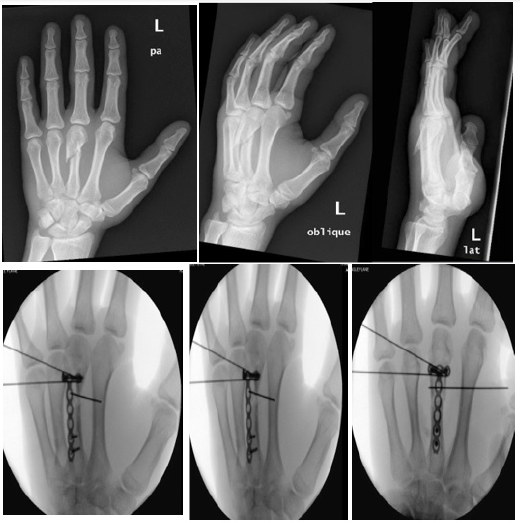

29-year-old patient sustained trauma to left hand at work, presented 1 month later with extension lag + dorsal tender swelling. X-ray confirms comminuted metacarpal fracture with dorsal displaced bone spike Surgical intervention is planned through open approach. Upon opening, there were 3-4 fractured pieces with unable to reduce and fix via conventional 1mm K wires because there was pulling forces pushes the distal half proximally which causes significant overlap and shortening of the long finger [2].

Distraction of the fracture done through placing T Plate and 4 screws, which showed restoration of the finger length and normal cascade. Placing of 3k wires done afterwards to fix the small fractured pieces in place pre and post op x-rays are shown below.

Early mobility has been started with full restoration of range of movement by 8 weeks (Figure 1 & 2)

Figure 1:Pre and intra operative pictures (pre and post fixation).